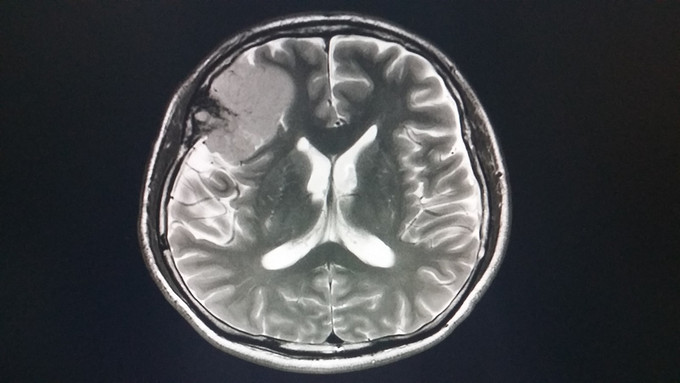

1、患者 男 67岁 体检发现颅内占位病变2月,右侧肢体麻木、头晕10天;既往有高血压病史 2、患者2月前体检行头颅CT检查发现右侧脑膜留,未做特殊处理,10天前无明显诱因出现右侧肢体麻木,头晕,饮水呛咳,口水及吃饭难于下咽,到当地医院就诊查头颅MRI:右侧蝶骨脊脑膜瘤可能,延髓偏左侧出血,海绵状血管瘤可能。

3、神清,伸舌居中,咽反射双侧消失;四肢肌力5级,右侧肢体感觉减退 4、头颅MRI:右侧蝶骨脊脑膜瘤可能,延髓偏左侧出血,海绵状血管瘤可能

5、入院诊断:1.右侧蝶骨脊脑膜瘤 2.海绵状血管瘤 6、完善术前相关检查,在全麻下行脑膜瘤切除术及延髓段海绵状血管瘤夹闭术,考虑到延髓为呼吸循环中枢术后入重症监护室治疗,予以心电监护及呼吸机辅助呼吸,密切关注患者生命体征。